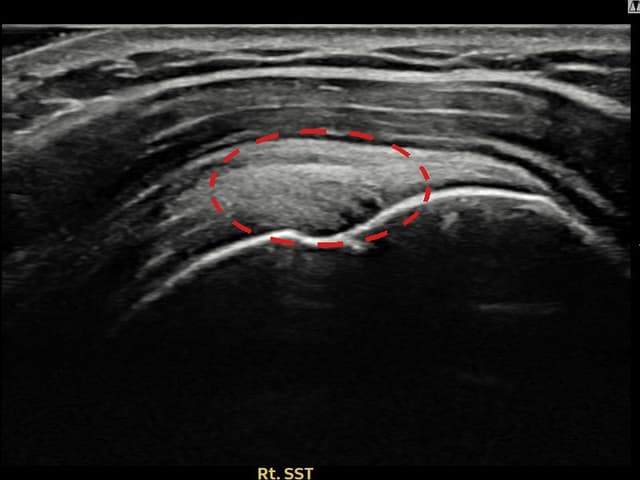

[経過期間: 23.07.31~23.09.27]

[縫縮術] 超音波検査にて左 棘上筋腱 부착부 광범위 部分断裂(13mm × 5mm (腱厚の約65%欠損))を確認。縫縮術施行後、腱の連続性が回復し、日常生活に復帰されました。